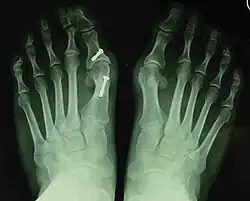

- For recurrence correction after osteotomy procedure (Fig. 8)

Late deformity recurrence can happen after osteotomy (bone-breaking) procedures because osteotomy surgeries do not specifically stabilize first metatarsal bone.

For recurrence correction after fusion procedure (Fig. 9) Metatarsus primus varus deformity and pain recurred 6 months after modified Lapidus procedure and it could also be again corrected by the syndesmosis procedure.